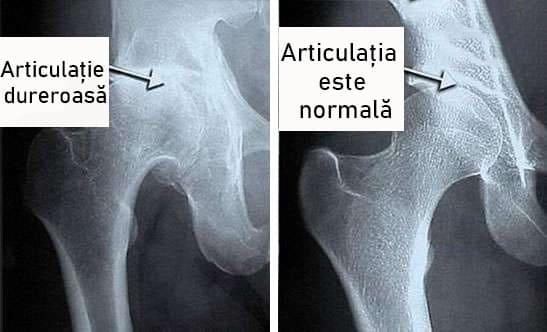

Și acestea sunt fotografii ale articulațiilor “înainte” și “după” tratamentul Steplex :

Lukaa Russu : “Fotografiile arată clar că Steplex nu numai că ameliorează durerea, ci și declanșează regenerarea lichidului sinovial, ceea ce ar trebui să facă condroprotectorii. Ca urmare, stratul de cartilaj devine mai larg și mai elastic – articulațiile se vindecă, durerea și rigiditatea dispar.